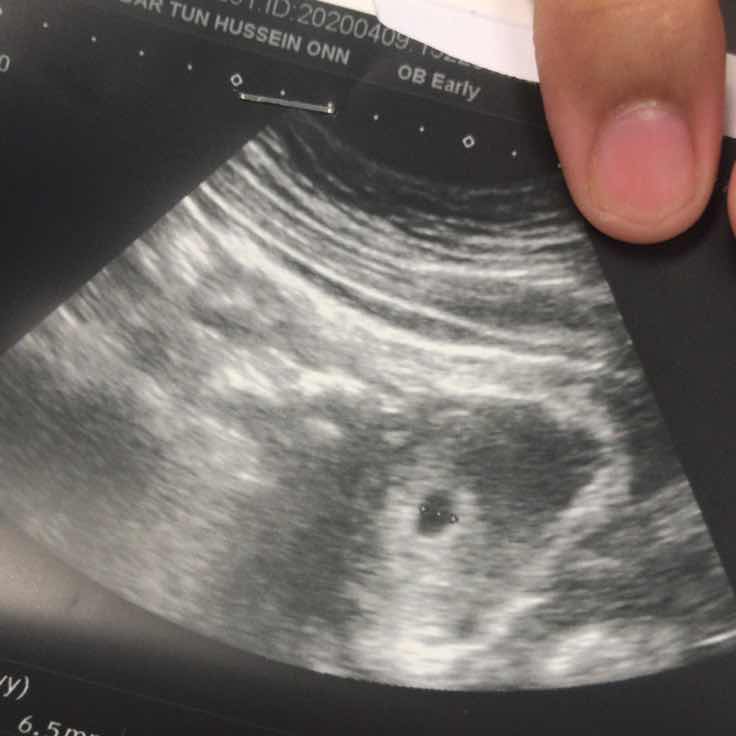

Nampak kantung je

Salam mommies ada pengalaman tak scan masa 6 weeks hanya nampak kantung je. Normal ke?

Saya punya 6 weeks scan. Menang nampak kantung je, lepas 2 minggu baru nampak baby hehe.

Saya pun sama, 6 weeks tapi nmpak kantung ja... DR cakap mungkin kandungan kecil lg